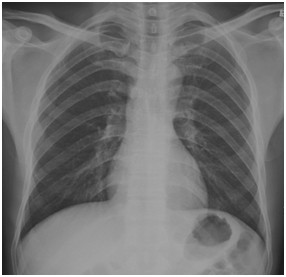

临床助理医师实践技能考试模拟试题:“ X线-正常胸片 ”影像诊断!

2022-03-29